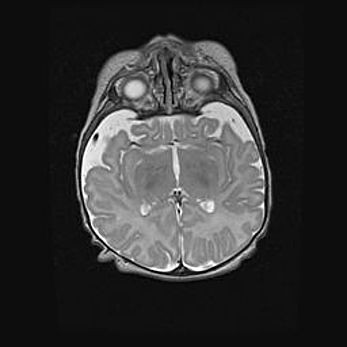

Подострая гематома правой гемисферы мозжечка.

Наружная гидроцефалия.

Возраст: 15 дней

Вес: 3100 г

Пол: женский

Окружность головы: 37 см

Срок гестации: 35-36 недель

При открытой наружной форме гидроцефалии у новорожденных расширяются и переполняются субарахноидные пространства.

Кровоизлияния в мозжечок имеют две клинико-анатомические формы: полушарные гематомы и кровоизлияния в червь.

К появлению этой патологии может привести: повреждения головного мозга, возникающие в результате асфиксии и гипоксии плода при беременности, или травмы во время родов. Редко гематома мозжечка может быть результатом первичной коагулопатии и сосудистой мальформации, диссеминированном внутрисосудистом свертывании, изоиммунной тромбоцитопении.